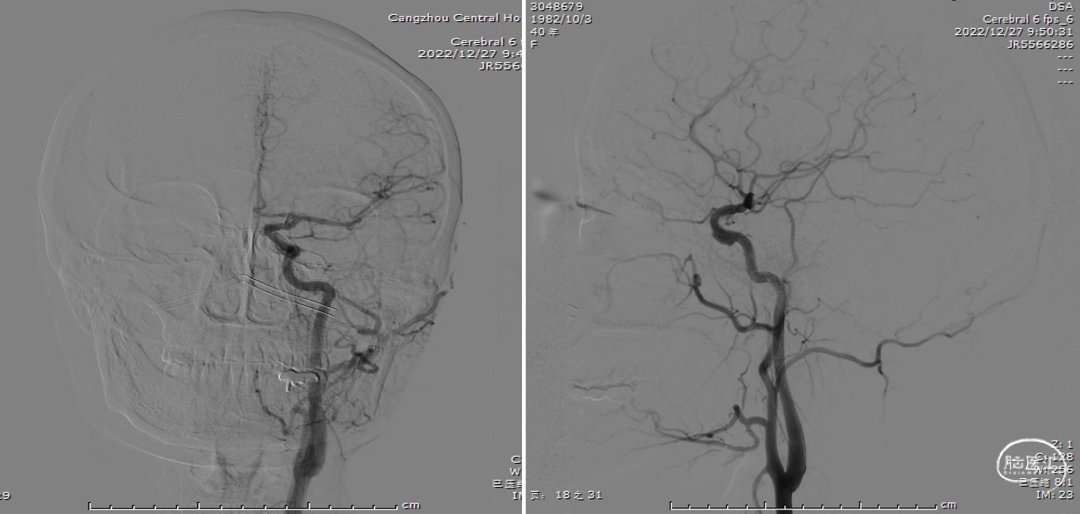

术前造影

术前CTA

全脑血管造影(2022-04-13)

右颈内动脉3D重建(海绵窦段宽径7.2mm)

全脑血管造影

左颈内动脉3D重建图像(眼段宽径7.8mm)

左颈内动脉3D重建图像(海绵窦段宽径6.5mm)